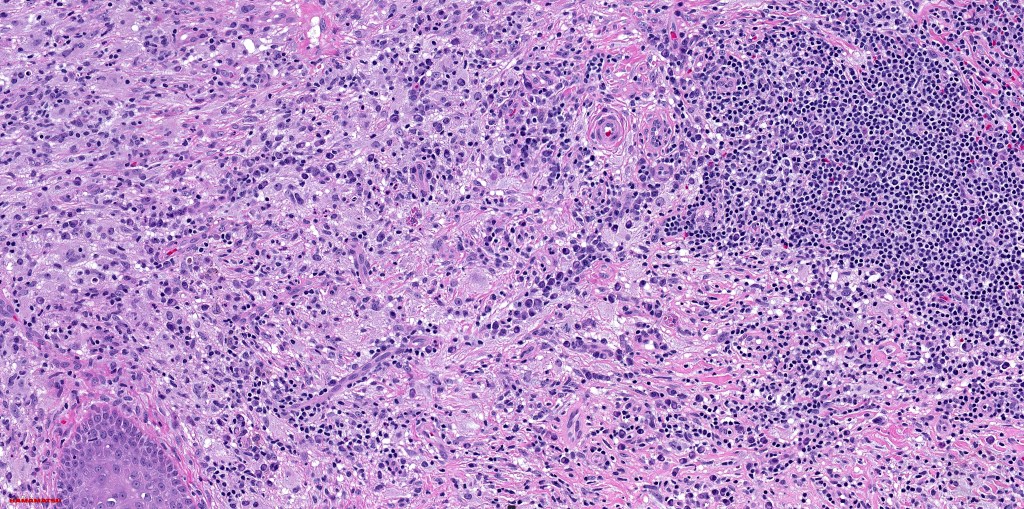

•Due to the admixture of pale histiocytes and lymphocytes, the scanning view is characteristic, and the diagnosis can be strongly suspected at this magnification

•Dense dermal nodular infiltrate sometimes extending into subcutaneous fat

•Lymphoid follicles with germinal centers sometimes present

•Fibrosis is occasionally conspicuous